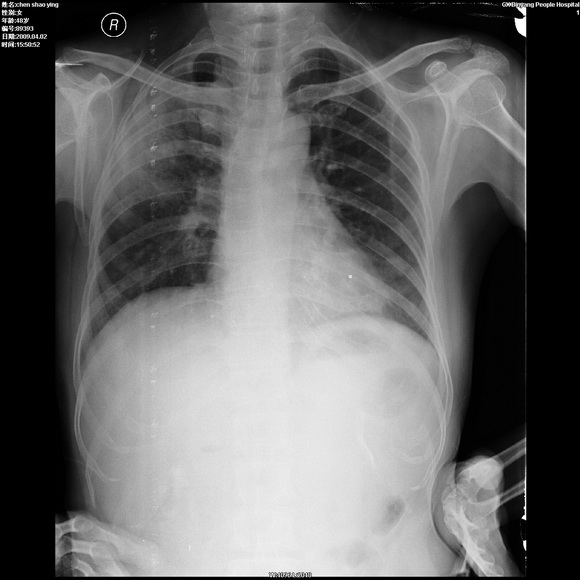

患者,女,48岁,发热伴陈发性咳嗽5天,偶尔痰中带血。体温约38°~40°;白细胞明显减低0.85x10的9次方/升。入院后抗炎、抗痨一周复查病灶明显进展。

右上肺后段实变影,内见支气管气象,肺门未见软组织肿块,气管前方有肿大淋巴结。左下肺见多个类圆形结节影。考虑:1.右上肺后段大叶性肺炎,需进一步检查病原体种类,应多询问病史,条件许可考虑做纤支镜检查2.左下肺结节影性质待定

考虑右上肺后段大叶性肺炎不除外结核,伴双肺结节播散灶,希定期复查。

问题是抗炎治疗一个星期后病灶进展。

右肺于酪性肺炎并左肺播散。

考虑两肺继发性肺结核(右肺上叶干酪性肺炎)。

右肺干酪性肺炎并左肺播散。

右肺片状实变影,左肺结节影,抗炎及抗捞治疗后病灶进展。

我考虑:不能除外肺炎型肺泡癌可能。建议查痰或活检。